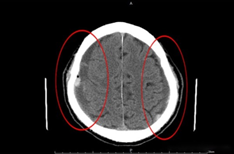

陳男經電腦斷層檢查後,發現腦部雙側硬膜下血腫(紅圈

陳男經頭部電腦斷層檢查發現腦部雙側硬膜下血腫、壓迫腦實質安排住進加護病房接受治療,給予安排術前其他各項檢查及經麻醉科評估後,由陳副院長執行雙側顱骨穿孔引流手術移除血腫,3日後移除頭部雙側引流管,隔日轉至外科病房治療。陳男家屬表示,術後頭暈及耳鳴已有明顯改善,右手可以扣釦子及自行使用餐具進食生活上可自理,少見抖動情形,下床行走時也不再搖搖晃晃。7日後安排患者追蹤頭部電腦斷層檢查發現雙側硬膜下血腫大幅減少後辦理出院回家調養。